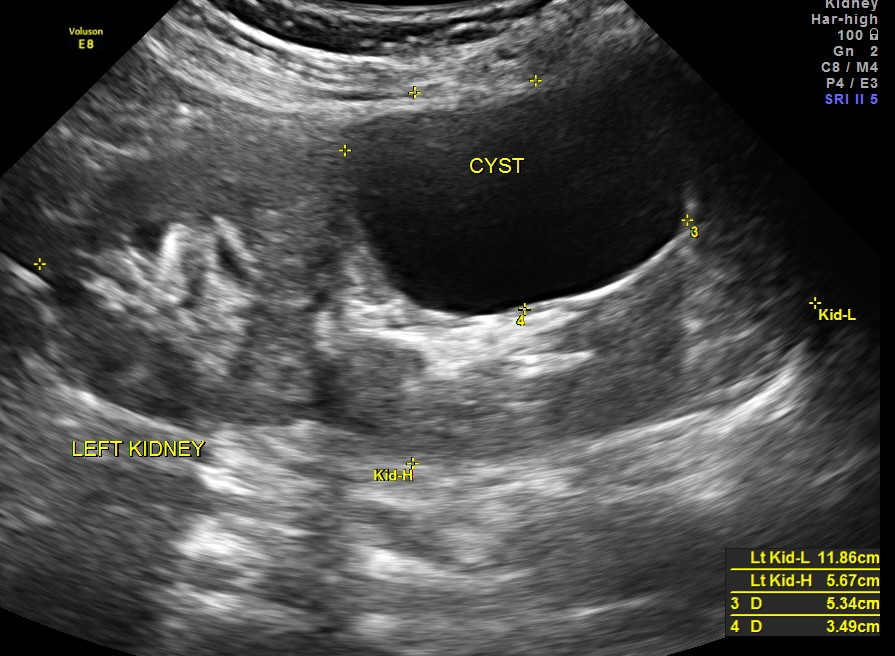

The left kidney showed an incidental simple cyst.